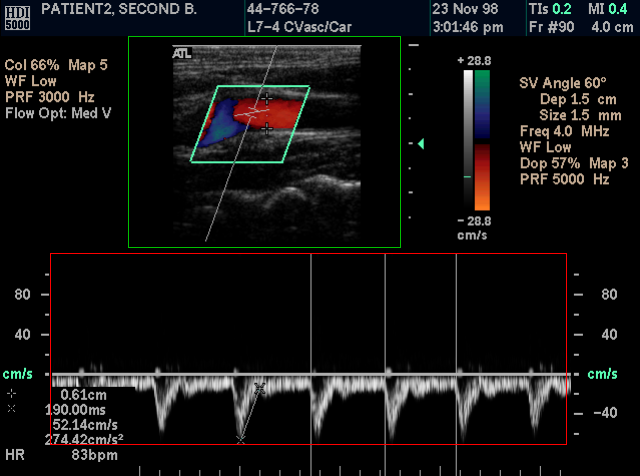

Take calibrated Ultrasound measurements

The program supports the Ultrasound Region Calibration Module (0018, 6011), and it can take calibrated distance and area measurements in ultrasound DICOM files.

When the user selects the distance measurement tool, one or more rectangles appear on the image. Each one of these rectangles represents a calibrated region. The active region has a green color and the inactive regions have a red color. Within the active (green) region the mouse cursor has a cross shape, and within the inactive (red) region has an arrow shape. The user can take measurements in the active region.

The user can easily check the accuracy of the measurements by taking the same measurement in the ultrasound machine and in the program.